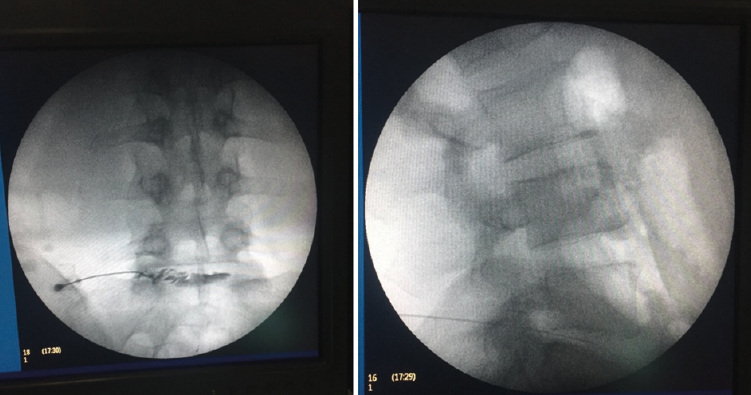

Entre las principales indicaciones de la TAC, se incluirían la sospecha clínica de hernia discal (Figura 12)(26), la estenosis del canal vertebral lumbar, la fractura vertebral lumbar, los tumores vertebrales, la valoración posquirúrgica tras una cirugía de artrodesis vertebral lumbar y la sospecha de una sacroileitis en el contexto clínico de una posible espondiloartropatía inflamatoria. También es muy útil como herramienta auxiliar en determinados procesos diagnósticos, como por ejemplo en la biopsia de una zona sospechosa y en el diagnóstico postoperatorio de la correcta colocación de implantes en la columna vertebral.

Al igual que en la radiología simple, muchos pacientes asintomáticos presentan imágenes anormales en la TAC. En el estudio de Wiesel et al.(25), más del 35% de las TAC de columna lumbar en personas asintomáticas eran patológicas. Por ello, los expertos advierten de la necesidad de correlacionar adecuadamente los hallazgos de la TAC con la sintomatología referida por el paciente.

La sobrevaloración de las imágenes sin una correcta valoración clínica puede conducir a errores diagnósticos y terapéuticos de importancia, oscilando desde restricciones severas de la actividad física y laboral, indicaciones terapéuticas o rehabilitadoras inadecuadas, y hasta intervenciones quirúrgicas no indicadas.